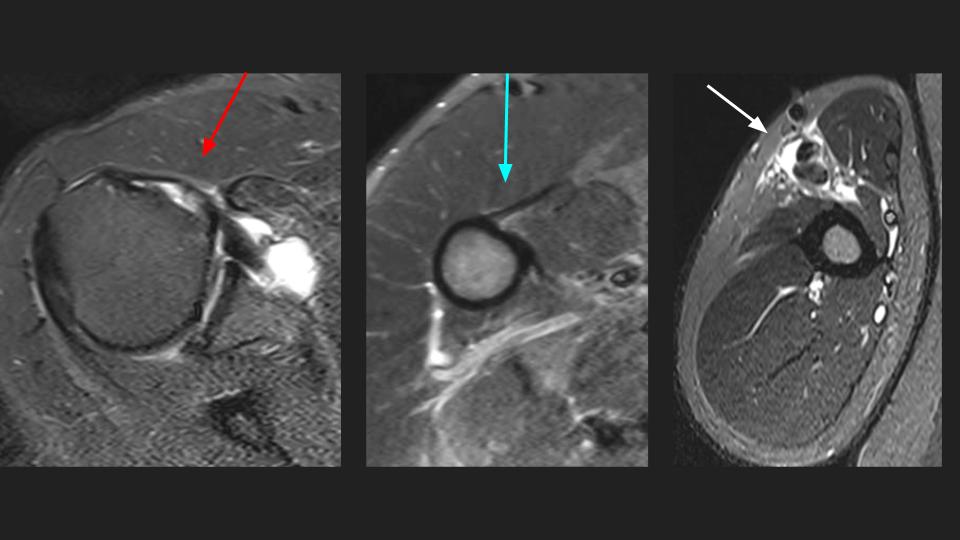

58M shoulder and upper arm pain x 4 weeks

There is a complete tear of the intraarticular long head biceps tendon (LHBT). The intraarticular remant is displaced into the superior subscapular recess and the torn retracted tendon is distal to the pec major insertion (bue arrow) in the mid upper arm (white arrow). Note the delaminating tear of the subscapularis tendon (red arrow). There is moderate supraspinatus tendinosis without tear (not shown).

tendon of long head of biceps brachii ( RID1944 )